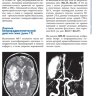

Примеры страниц из книги "Нейросонология и нейровизуализация при инсульте" - Вальдуэза Х. М., Шрайбер С. Й., Рёль Й. -Э., Клингебиль Р.